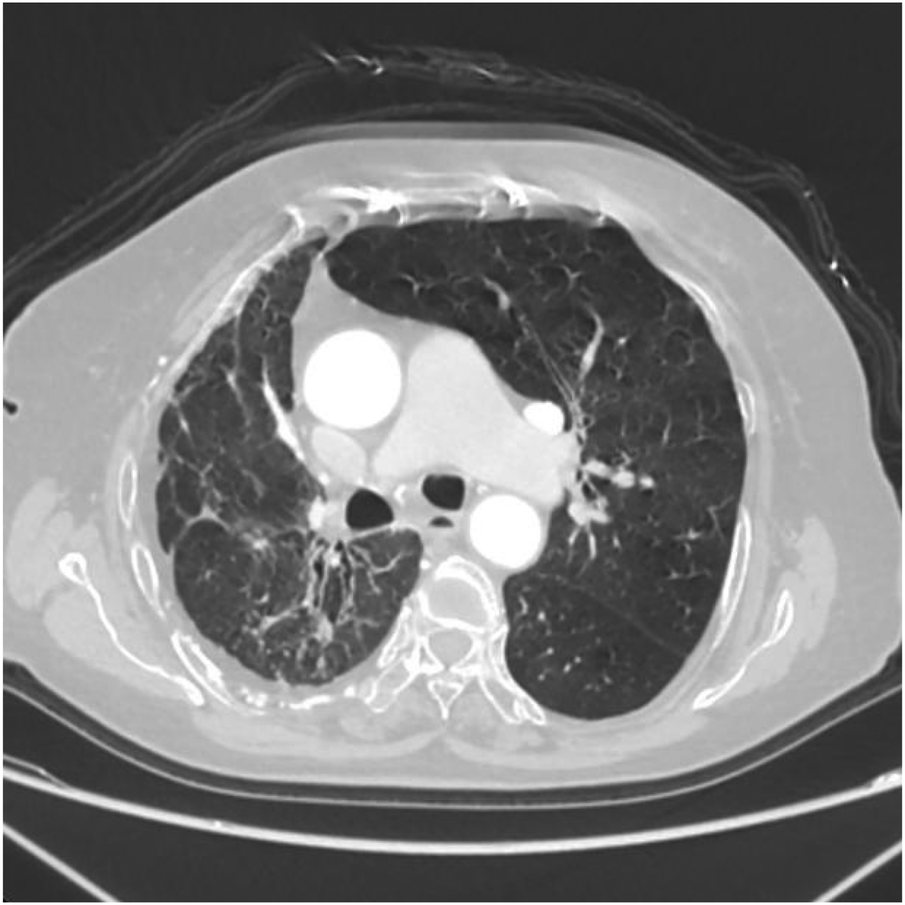

Figure 9

Axial image shows narrowing of the right thoracic cage, reduction in right lung volume, and patchy increased density shadows in the upper lobe of the right lung.

Figure 10

Axial image shows bronchiectasis in the right lung with surrounding inflammation and linear opacities, thickening of the right pleura, and rightward shift of the trachea and mediastinum.

Figure 11

Axial image shows partial bronchiectasis in the right lung, partial inflammation and linear opacities in the right lung, thickening of the right pleura, and rightward shift of the trachea and mediastinum.

Figure 12

Axial image shows pulmonary emphysema in the left lung with multiple bullae.

Thoracoabdominal aortic CTA and chest CT findings are illustrated in Figures 1–14. There was no evidence of aortic dissection. The right pulmonary artery was absent distal to approximately 3 cm from the bifurcation, with a smooth and rounded defect margin. The main pulmonary artery and its major branches showed no abnormal densities. No right pulmonary artery branches were observed in the right lung. Multiple tortuous arterial branches from the right subclavian artery, descending aorta, and right renal artery supplied the right lung. The right hemithorax was smaller, with localized pleural thickening and adhesions bilaterally. Multiple bronchiectasis with thickened walls and patchy, nodular, and linear opacities encircled the right lung. Increased translucency and several hyperlucent regions were visible in the left lung. CT imaging findings demonstrated: 1. Congenital absence of the right pulmonary artery (RPA), with the right lung supplied by collateral circulation originating from the right subclavian artery, right intercostal arteries, and the right renal artery. 2. Right pulmonary hypoplasia, bronchiectasis of the right lung, accompanied by infection and partial consolidation in the right upper lobe, compensatory hyperinflation of the left lung, and multiple bullae in the left lung. 3. Bilateral localized pleural thickening and adhesions. 4. Osteoporosis and mild flattening of the T6 vertebra and compression fractures of T11 and T12.